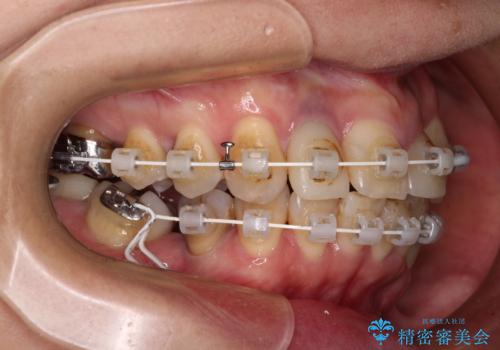

他にも奥歯の咬み合わせに問題があったので、全顎的な矯正治療を行い、前歯以外にも口を開けたときに目立つ奥の銀歯をセラミッククラウンにて補綴治療を行うこととしました。

前歯の横幅が大きいことも気になっていたので、矯正治療で前歯5本の幅をコントロールしながら移動させ、治療開始前より一回りサイズの小さいセラミッククラウンを装着することができました。